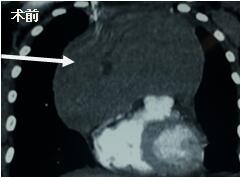

當(dāng)看到病人的CT等外院各項檢查時,我頭皮發(fā)麻�,心頭發(fā)怵:巨大的腫塊占據(jù)著整個縱隔����,壓迫心臟�����,與血管關(guān)系密切���,初步考慮侵襲性胸腺瘤、胸腺癌或淋巴瘤等�����,合并腎功能不全��,無法完整切除,手術(shù)風(fēng)險大�,手術(shù)并不能提高病人長期生存率�,換言之,小伙子等待的是生命的立即終結(jié)。

當(dāng)我們積極行術(shù)前準(zhǔn)備��,制定手術(shù)預(yù)案���,行手術(shù)時�����,麻醉科段雪琴主任并沒有因為病情危重�,插管困難��,氣管塌陷等可預(yù)見危險而停止手術(shù)�。相反,聯(lián)系呼吸內(nèi)科,共同行氣管鏡插管�,事實上,麻醉過程驚心動魄��,受壓的氣管幾乎導(dǎo)致插管失敗�����,持續(xù)的缺氧讓我們?yōu)椴∪松钅罅艘话押埂?BR>當(dāng)我們有條不紊地打開胸腔�,滿視野的腫瘤讓人汗毛倒豎,當(dāng)一點一塊切除腫瘤��,患者的癥狀逐漸緩解����,缺氧改善,生命體征趨于平穩(wěn)后�����,我們幾乎癱坐在凳上�,那緊繃的弦才稍有松弛。

當(dāng)看到病人癥狀緩解�,復(fù)查胸部CT幾近完美�����,我們那種自豪感油然而生�����。偶爾去治愈,常常去幫助��,總是去安慰�,我們深知,小伙子的人生之路并不長����,只能深深祈禱他在我們的治療下能走得更遠(yuǎn)一些,能把剩下的日子走的更充實一些����。而我們在能夠幫助人的時候�,別一味地去安慰,永不言棄���,是我們這一群胸外人堅貞的信念。